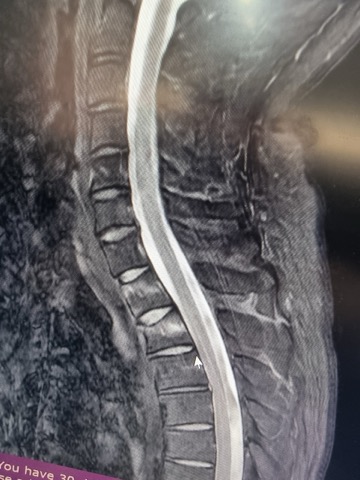

MRI, X-Ray 가지고 있는 사진 첨부했습니다.

무릎 골절, 견갑골 골절, 무릎인대 파열, 대퇴골의 골절, 경골 골절, 흉추 골절, 다발의 타박상, 다발의 찰과상, 뇌진탕